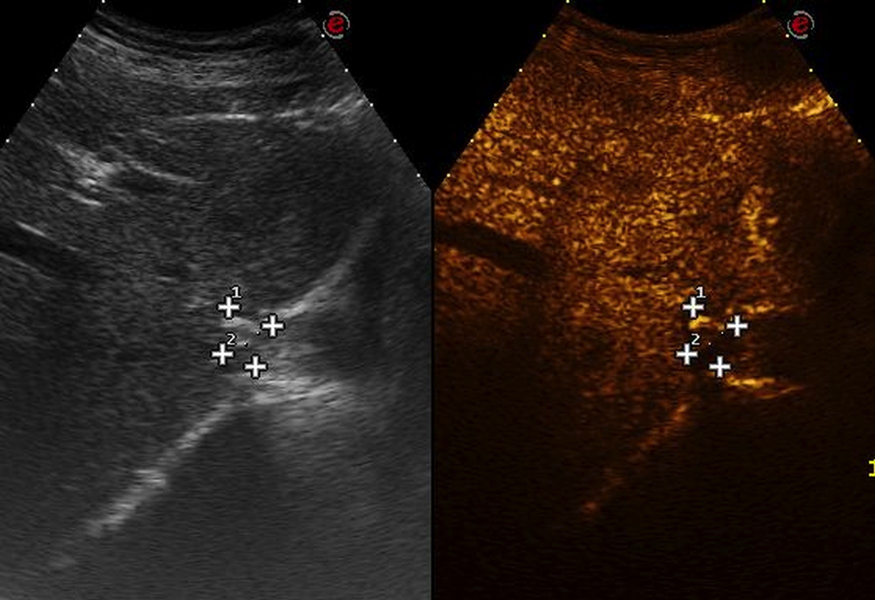

Un paziente con una metastasi al fegato di 8 mm nel segmento I particolarmente vicino al pericardio è stato sottoposto a Termoablazioen con EchoLaser. La lesione è stata ablata completamente senza nessuna complicazione legata alla struttura critica vicina come il versamento pericardico.

Immagine CEUS post trattamento che mostra una completa ablazione

Immagini per gentile concessione del Dott. Sergio Sartori (Ospedale Sant’Anna, Ferrara)